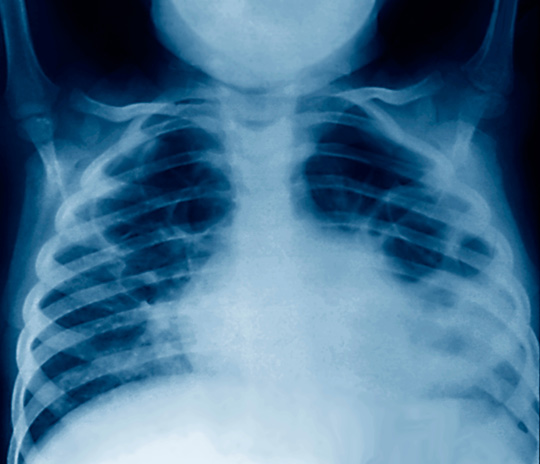

Lungebetennelse blant sørafrikanske barn

Forekomsten av lungebetennelse synes å være høy blant barn i Sør-Afrika, til tross for et nasjonalt vaksinasjonsprogram med blant annet pneumokokkvaksine.

Lungebetennelse er fortsatt den sykdommen som tar livet av flest barn på verdensbasis. I en kohortstudie fra Sør-Afrika er insidensen, alvorlighetsgraden og risikofaktorer for lungebetennelse i første leveår undersøkt (1). Studien pågikk i perioden 2012 – 14 og omfattet 697 barn rekruttert fra to klinikker i nærheten av Cape Town.

Diagnosen pneumoni ble stilt hos barn med hoste eller pustevansker og aldersspesifikk takypné eller hvis det ble observert respiratoriske inndragninger i brystkassen. Vaksinasjonsdekningen blant deltakerne var høy for vaksiner gitt de første tre levemånedene, men sank til 75 % for den tredje dosen av en 13-valent pneumokokkvaksine som gis ved ni måneders alder.

Det ble registrert totalt 141 tilfeller av lungebetennelse i første leveår, hos 109 av studiedeltakerne. Av disse var litt under en firedel kategorisert som alvorlige tilfeller. Ut fra dette ble insidensen av lungebetennelse hos barn under ett år beregnet til 0,27 episoder per personår (95 % KI 0,23 – 0,32). To barn døde som følge av lungebetennelse.

Forskerne fant at hivsmitte hos mor, røyking hos mor, underernæring hos barnet og det å være gutt var assosiert med høyere risiko for lungebetennelse i første leveår. De konkluderer med at forekomsten av lungebetennelse i første leveår var høy og anbefaler sterkere innsats rettet mot risikofaktorene.